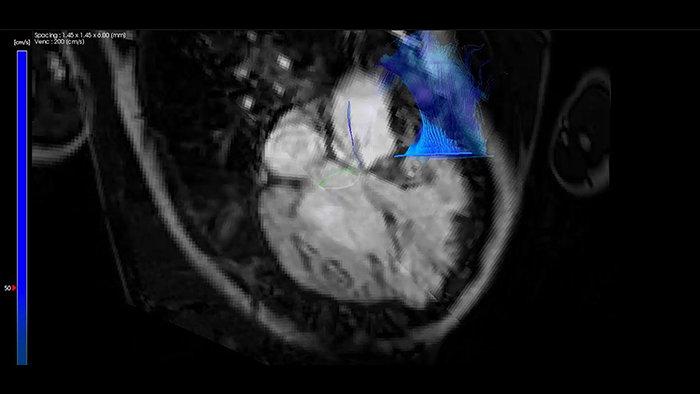

Orientação em tempo real do SmartCT

IntelliSpace Portal MR Caas 4D Flow em Tetralogia de Fallot